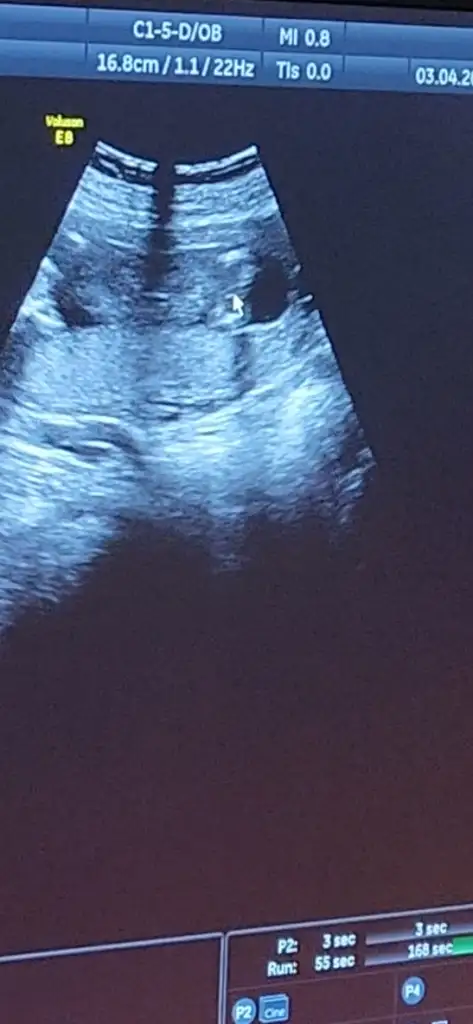

Kızlar bana 13de özelde yuzde 60kız denmişti sonra devlete gittim 15de yüzde 99erkek denmişti bu gün özeldeki hastaneye gittim doktor inat ediyor bu bebek kız diye 🫣🤣 tekrar devlete başka bir doktora gittim oda yüzde 80erkek dedi ee hocam devlete gittim yüzde 80erkek dediler dedim yat bida bakalım dedi yok bu bebek kız diyor şaşırdım kaldım yaa

Aynen öyle oldu 🤣 özeldeki doktorun tecrübesini inanıyorum ama ultrason cihazı karanlık pek net deyil devletteki iki doktorun da cihazı biraz daha net gibi görüntü ve çıkıntıyi gördüm bu gün yüzde 80erkek diyen doktor da gördü çıkıntıyı yüzde yüz diyemem bu çıkıntı klitoris de olabilir henüz net olmamakla beraber erkek dedi hele diğeri yüzde 99erkek dedi ya çıknti var ama ne olduğu belli deyil sinir oldum

Özeldeki bacak arası boş diyor ama devletteki iki doktorda da gördüm çıkntıyı ama o çıknti klitoris de olabiliyormus heralde wallahi de billahi de hiç önemli deyil kız olsun erkek olsun ama net olmayınca sabah beri aklimda kizmi erkek mi diye dönüp duruyor 20.ci haftada detaylida kesinleşir herhalde

🫣 Ya benide hem bi gülme aldı hemde bi sinir bastı nasıl oluyorda anlamıyorlar 16.cı hafta şaka gibi.Kız pipiyi de gördüm yani 2kere 🤣 o pipi değildir belki kordon dolamistir yada klitoristir diyor çok emin kendinden yanılmam ben diyor başka birşey demiyor devletteki de yüzde 99dedi bir ihtimalide öylesine veriyorum demisti.İkili test sonucum temiz çıktı en önemlisi saglik wallahi doğru düzgün sevincini yaşayamadim biri kız diyor biri erkek 🤣🤣

Bu şekilde ogrendim en son nasıl gordu bilmiyorum genelde bacak arasına bakılır ama bizim ki bütün vücuttan baktı ondan tam guvenemedim🙄 şuan anlatabildim mi demek istediğimi bilmiyorum 😅